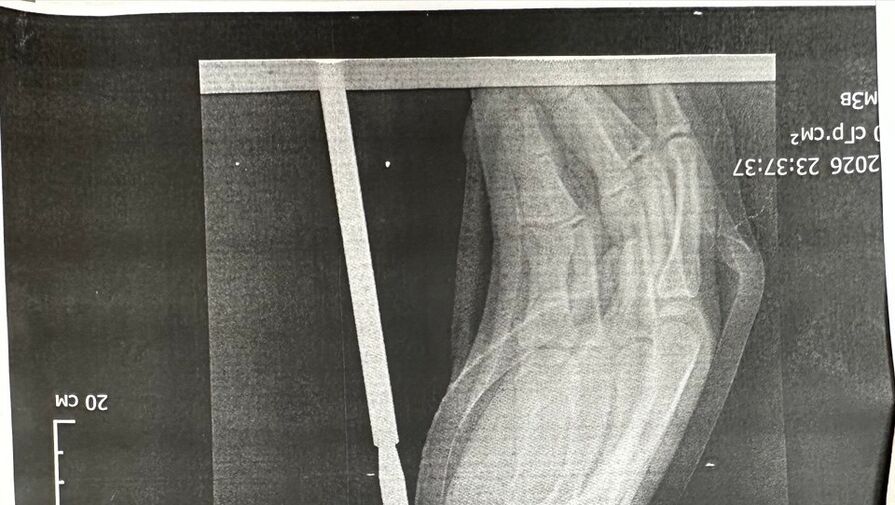

«Гарпун с двумя зубцами прошел между костями, не задев их. Специалисты извлекли инородное тело, обработали колотую рану и оказали пациенту квалифицированную помощь», — говорится в публикации.